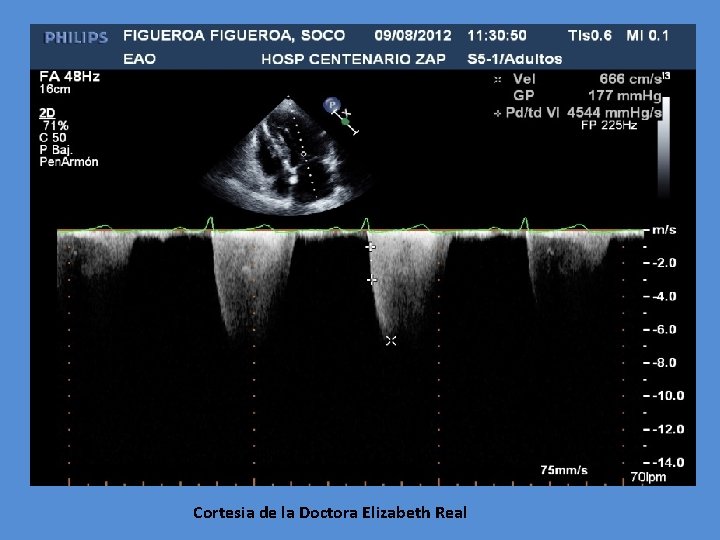

Cortesia de la Doctora Elizabeth Real

Indicación Qx en insuficiencia mitral importante Fracción expulsión <60% (aun asintomática cuando estrés sistólica VI elevada) Px c/HT Pulmonar y buena función del VD La calcula del dp/dt por tecnica de Doppler sigue siendo al parametro para la indicacion Qx, y es dependiente de precarga En insuficiencia Mitral, precarga esta aumentada, por lo que valor < 1, 200 mm. Hg/seg = reduccion de contractabilidad por sobrecarga Cuando es < 1, 000 mm. Hg/seg = Fraccion ejeccion es < 50% Cuando opera oportunamente = mortalidad es baja (2 -4%) J. F. Guadalajara 6 a Edition, Mexico, Mendez Editores, 2006, Cap. 17, pg. 556 -615